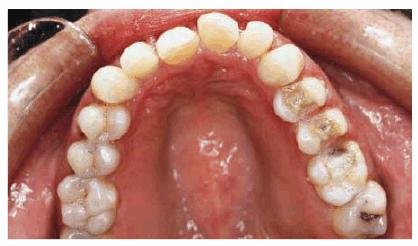

RESULT: By comparing occlusal views, one can see how effective the two

procedures were in creating the illusion of straightness (see Figures 24-3F, and 24-3G). A more proportional smile can be

seen by comparing Figures 24-3H, and 24-3I

Figure 24-3G: Final result shows a straighter arc with more proportional teeth.

Figure 24-3H: Pretreatment view of the smile.

Figure 24-3I: Post-treatment view showing better harmony with the smile.